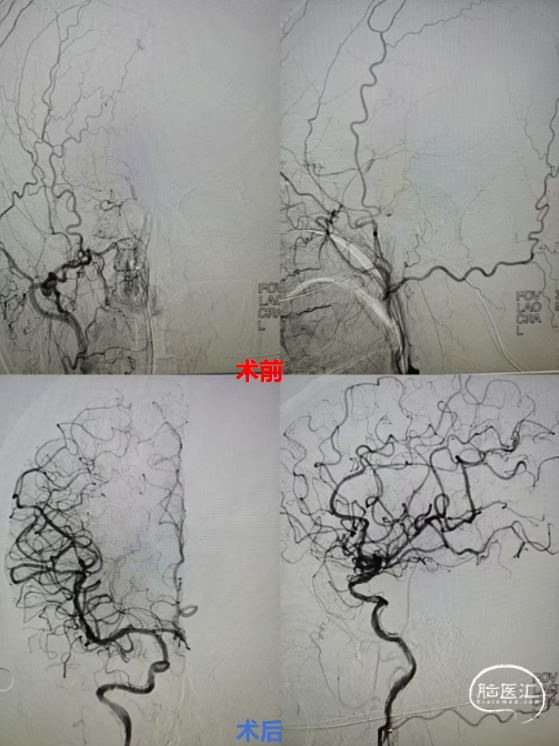

DSA造影(2024.11.07)

右侧颈内动脉起始段闭塞,动脉晚期可见颈动脉颅内段浅淡显影。

前交通动脉开放,右侧大脑中动脉显影良好。

右侧后交通动脉开放,右侧颈动脉颅内段浅淡显影。

术后成形良好

术后影像(2024.11.12)